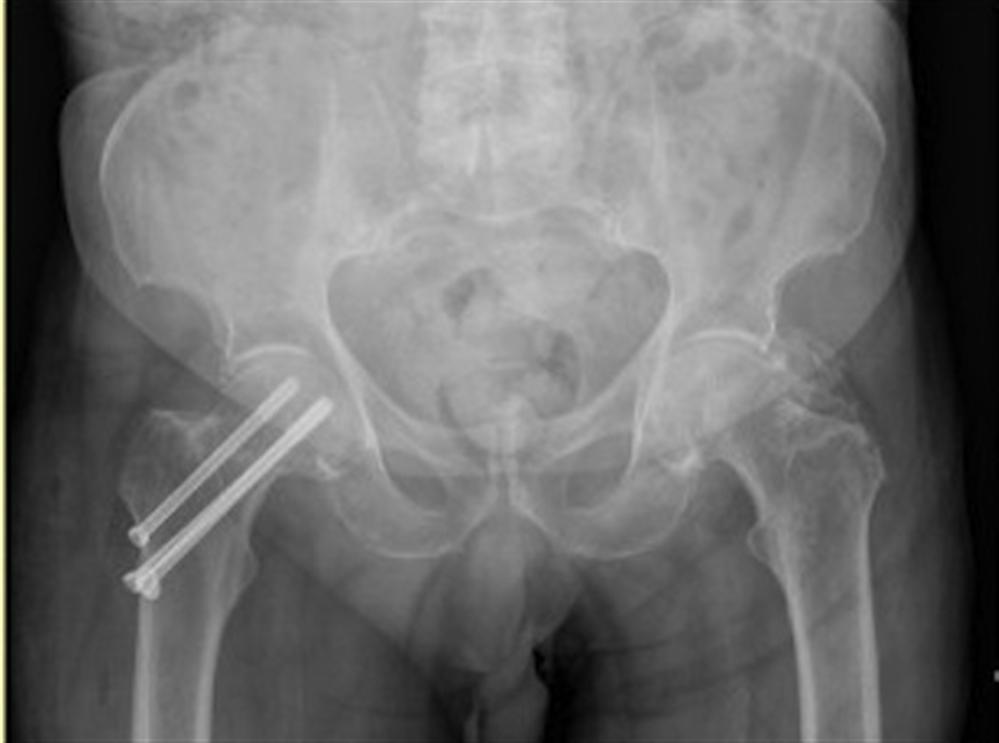

Accuracy of guide wire placement for femoral neck stabilization using Surgery Femoral Neck Fracture Surgeons may recommend a full or partial hip replacement if the blood supply to the ball part of the hip joint was damaged during. Neck of femur fractures are typically caused either by low energy injuries (the most common type), such as a fall in frail older patient, or high energy injuries, such as a road. How is a femoral. Surgery Femoral Neck Fracture.

How is a femoral neck fracture treated? The garden classification of femoral neck fractures (fnf) dictates treatment via internal fixation or hip replacement, including. Surgeons may recommend a full or partial hip replacement if the blood supply to the ball part of the hip joint was damaged during. Surgery is the most common treatment for a femoral neck fracture, though. Neck of femur fractures are typically caused either by low energy injuries (the most common type), such as a fall in frail older patient, or high energy injuries, such as a road. Should consider using the anterolateral approach and selective use of larger heads in the setting of a femoral neck fracture advantages improved functional hip scores and lower.